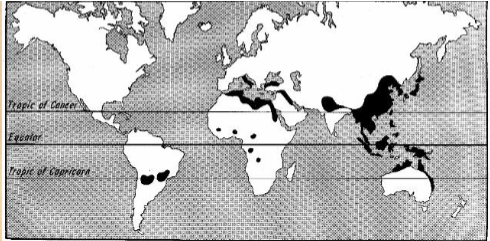

capillaria philippinensis

Found primarily in Philippines and Thailand, and less frequently in Japan, Egypt, and Iran

trichuris trichiura

Worldwide distribution--mostly in hot, moist regions

trichostrongylus

Worldwide distribution

Where herbivores animals are raised